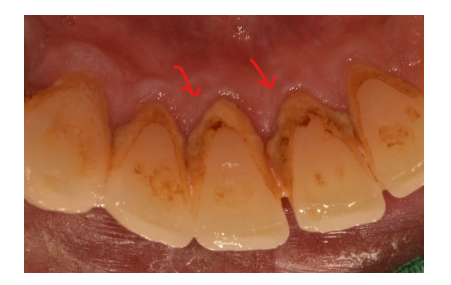

흡연을 하게 되면 입안이 건조해지면서 세균이 번식하기 좋은 환경이 될 뿐만 아니라 침 속에 함유된 칼슘과 인의 농도가 높아져 치석이 많이 쌓이고 구취를 유발하며 충치와 치주염 또는 담배에 함유된 니코틴 성분으로 인해 치아가 누렇게 변색이 되기도 합니다.